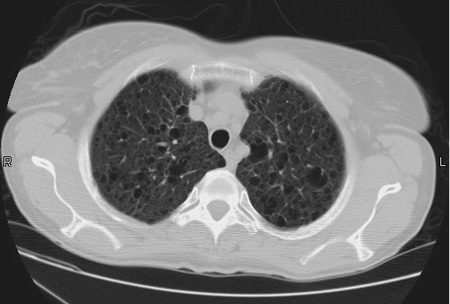

Scott WilliamsTumor Imaging[In-111-DTPA-D-Phe-] Octreotide:April 2, 2002CongenitalCongenital > CFApril 2, 2002AutoimmuneAutoimmune > IPFibrosis > DIPimagesApril 2, 2002Inhalation-LungsInhale > Asbestos > Images > Round atelectasis case 1April 2, 2002AutoimmuneAutoimmune > EGApril 2, 2002EndocrineHyperparathyroidism:April 2, 2002PETPET > PET tumor imaging > Colon CancerApril 2, 2002Vascular AbnormalitiesVascular > PEApril 2, 2002Mediastinal MassesMediastinum > GermcellApril 2, 2002GenitourinaryGenitourinary > RefluxApril 2, 2002Previous PagePage 128 of 265Next PageTop StoriesPractice ManagementHPI: Radiology attrition varies by gender, specialty, and practice typeContinuing workforce trends such as increasing subspecialization and practice consolidation could affect the attrition rate.Radiation Oncology/TherapyASTRO: Short prostate SBRT reduces side effects, but not PSA levelsRadiation Oncology/TherapyASTRO: STAR has role in managing VT in cardiac patientsCT5-year CTC screening interval is appropriate for colorectal cancerSponsor ContentDigital Innovations Shaping the Future of Radiology